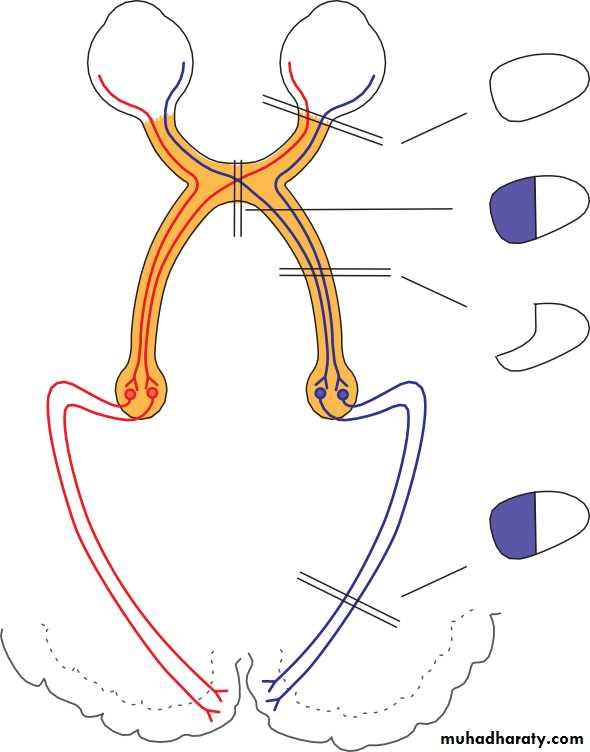

• Classification of the primary glaucomas (Fig. 10.2) is based on whether or not the iris is:

• covering the meshwork (closed angle).• PATHOGENESIS

• Chapter 10: Glaucoma• OPEN AND CLOSED ANGLE GLAUCOMA

Open angle• Iris

Trabecular meshwork

• Closed angle

Iris• Trabecular meshwork (covered by iris)

• Fig. 10.2 Diagram showing the difference between open and closed angle glaucoma.

• Closed angle glaucoma• The condition occurs in small eyes (i.e. often hypermetropic) with shallow anterior chambers. In the normal eye the point of contact between the pupil margin and the lens offers a resistance to aqueous entry into the anterior chamber (relative pupil block). In angle closure glaucoma, sometimes in response to pupil dilation, this resistance is increased and the pressure gradient created bows the iris forward and closes the drainage angle. These peripheral iris adhesions are called peripheral anterior synechiae (PAS). Aqueous can no longer drain through the trabecular meshwork and ocular pressure rises, usually abruptly.